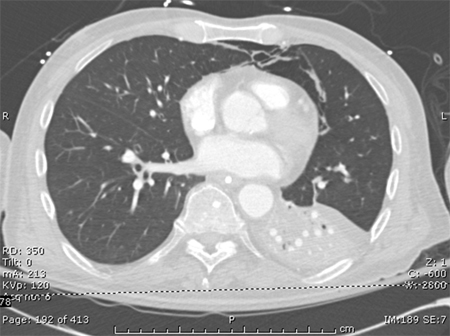

tomografia computadorizada (TC) do tórax

Uma tomografia computadorizada (TC) pode ser realizada para diagnosticar a opacidade e esclarecer se um procedimento é indicado.[Figure caption and citation for the preceding image starts]: Tomografia computadorizada mostrando opacidades bibasilares de paciente com pneumonia hospitalarConsentimento obtido na University of Louisville, Louisville, KY [Citation ends].

Resultado

pode mostrar opacidade ou esclarecer achados prévios quando a qualidade da radiografia for insatisfatória